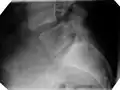

X-ray of a grade 4 anterolisthesis at L5-S1 with spinal misalignment indicated